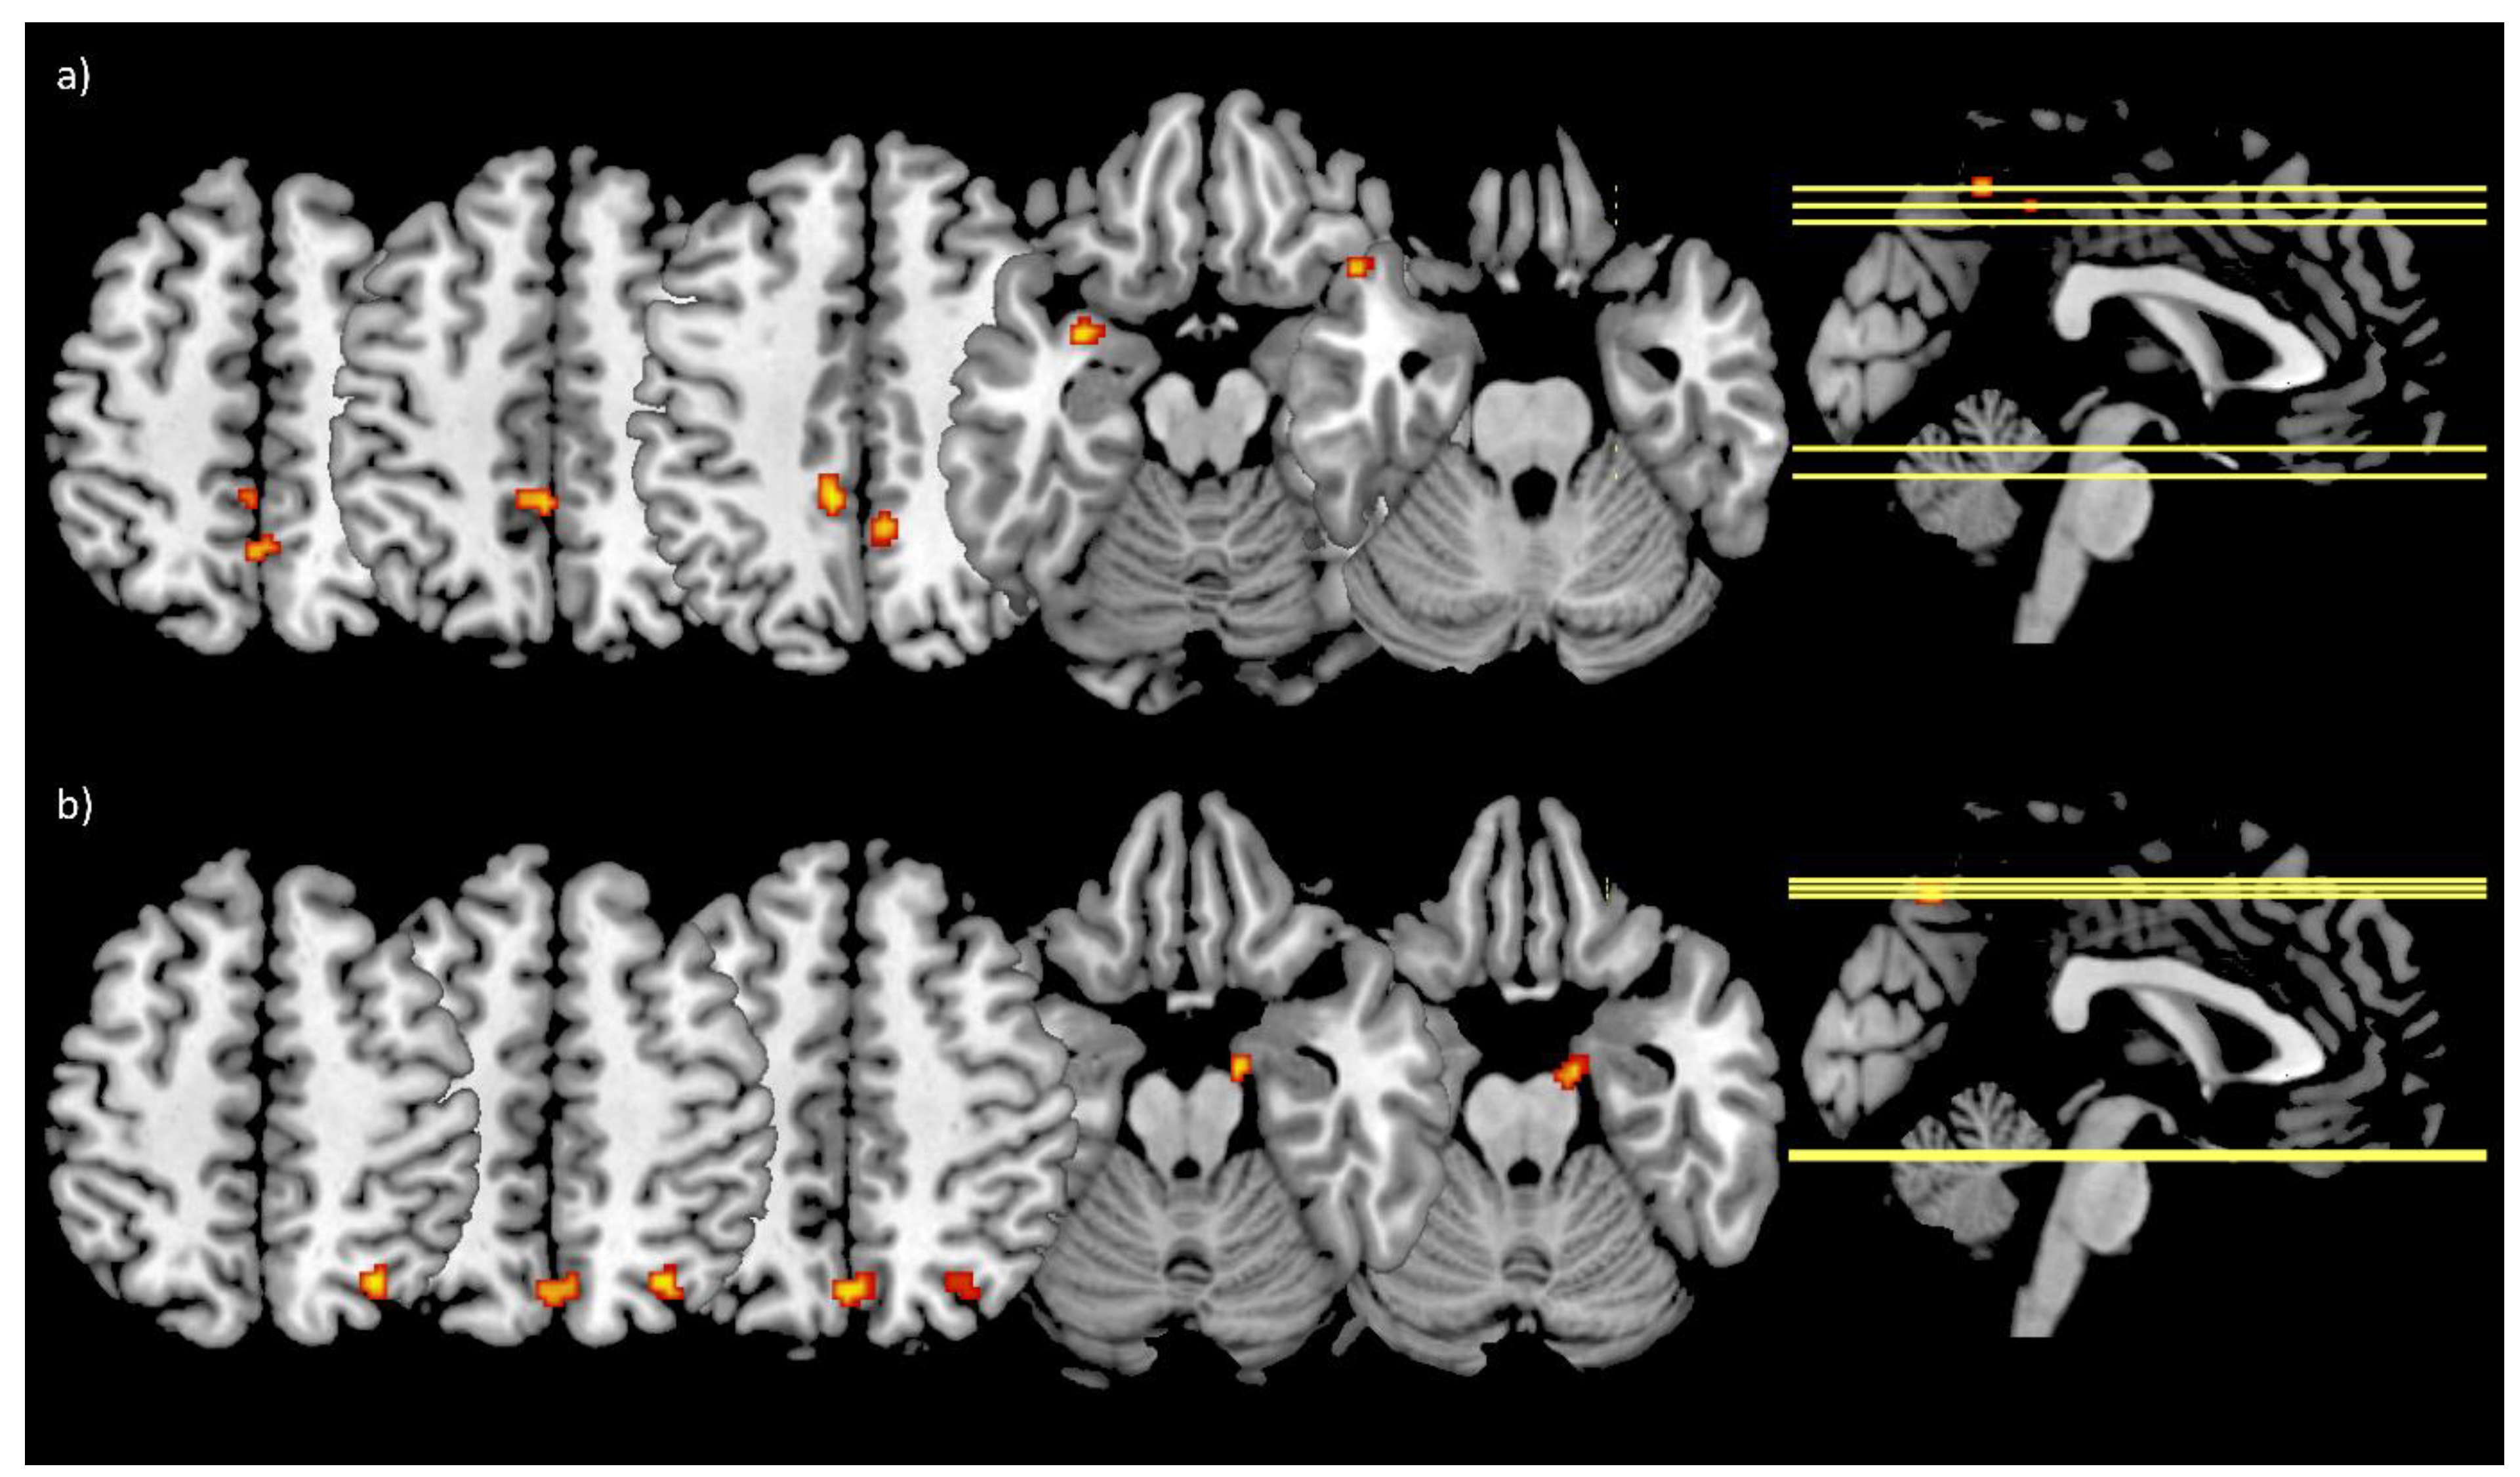

3.5. Functional Connectivity